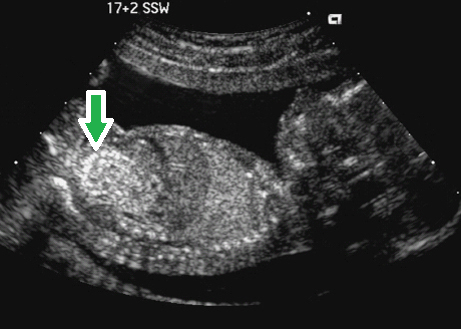

这是产前超声成像中的一个相当常见的异常软指标了,顾名思义,就是说看起来胎儿的肠道在 B 超下可以看到比较高的反射信号。如果是反射信号比肝脏高,可以算 I 级肠回声,如果反射信号更高,达到了骨骼的亮度,就要算 II 级肠回声。

肠道强回声本身其实并不是一种疾病,它只是肠道状况的一种表现。这种表现可以是由很多种原因引起的,比如说,是由于肠内有胎粪积聚;宫内环境有出血,血液被胎儿吞咽到肠道内;也可能是肠壁纤维化。还有一些其他原因,也可以引起肠壁的 B 超回声增强。在孕中期的胎儿中,我们有 0.2-1.8% 的几率会看到它,也就是大约每一百个胎儿里会有一到两个胎儿会有这种表现。

当遗传科医生看到肠回声增强时,首先一般都会告诉孕妈妈们,不用过度担心。目前的统计学数据表明,大约 70% 有肠回声增强的胎儿都是正常的。所以,大多数时候这种强回声都会随着胎儿的成长自行消失,不用做什么特殊治疗也会获得一个健康的宝宝。

但有肠回声增强明显,特别是信号达到 II 级的宝宝,根据医生们以往的观察,确实会有更大的可能伴随其他的问题,比如说之前提到的 21 号染色体三体综合征,又叫做唐氏综合征,或者是肠梗阻,巨细胞病毒感染,或者是囊性纤维化等其他先天遗传疾病。这样的胎儿,发生宫内生长迟缓甚至死胎的几率比普通胎儿要高出好几倍。如果除了肠回声增强,胎儿还有更多的 B 超或者其他指标异常,胎儿确实有异常的可能性就更大一些。